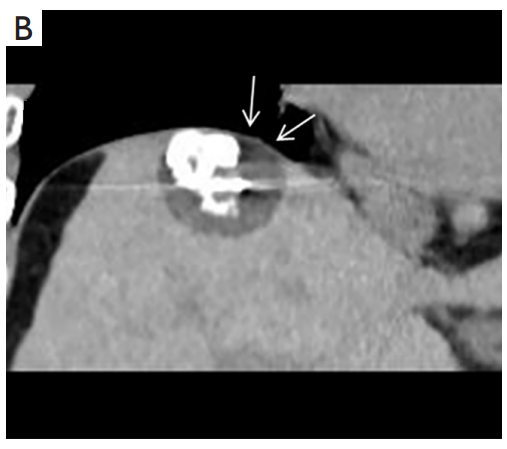

背景:肝癌是中國最常見的惡性腫瘤之一,發(fā)病率和死亡率都很高。雖然手術(shù)切除是最好的治療方法,但大多數(shù)患者處于晚期或直到住院才有手術(shù)指征。對于單個(gè)腫瘤直徑小于5厘米的患者,微創(chuàng)治療與手術(shù)切除效果相當(dāng);多個(gè)病灶小于3個(gè),單個(gè)病灶最大直徑小于3cm;不侵犯血管、膽管、鄰近器官和遠(yuǎn)處轉(zhuǎn)移。雖然一些傳統(tǒng)消融技術(shù)方式可以使部分患者受益,但不適用于特殊部位肝癌(定義為毗鄰大血管、肝外臟器和重要結(jié)構(gòu)的腫瘤)的治療。冷凍消融作為一種相對較新的治療方式,具有明顯的冰球效果、療效好、激活抗腫瘤免疫、并發(fā)癥發(fā)生率低等優(yōu)點(diǎn),尤其適用于特殊部位肝癌患者的治療。我們的研究目的是探討CA治療特殊部位肝癌的安全性、可行性和有效性。

① 在我們的研究中,技術(shù)成功率為100%。動(dòng)態(tài)增強(qiáng)MR檢查隨訪1個(gè)月,66例患者首次技術(shù)有效率為65例(98.5%),MR影像學(xué)未發(fā)現(xiàn)外周臟器損傷。中位隨訪時(shí)間14個(gè)月(范圍2-28個(gè)月)。高危部位肝癌局部腫瘤進(jìn)展率曲線:6、9、15和24個(gè)月的累積局部腫瘤進(jìn)展率分別為10.2%、16.5%、20.9%和30.5%。